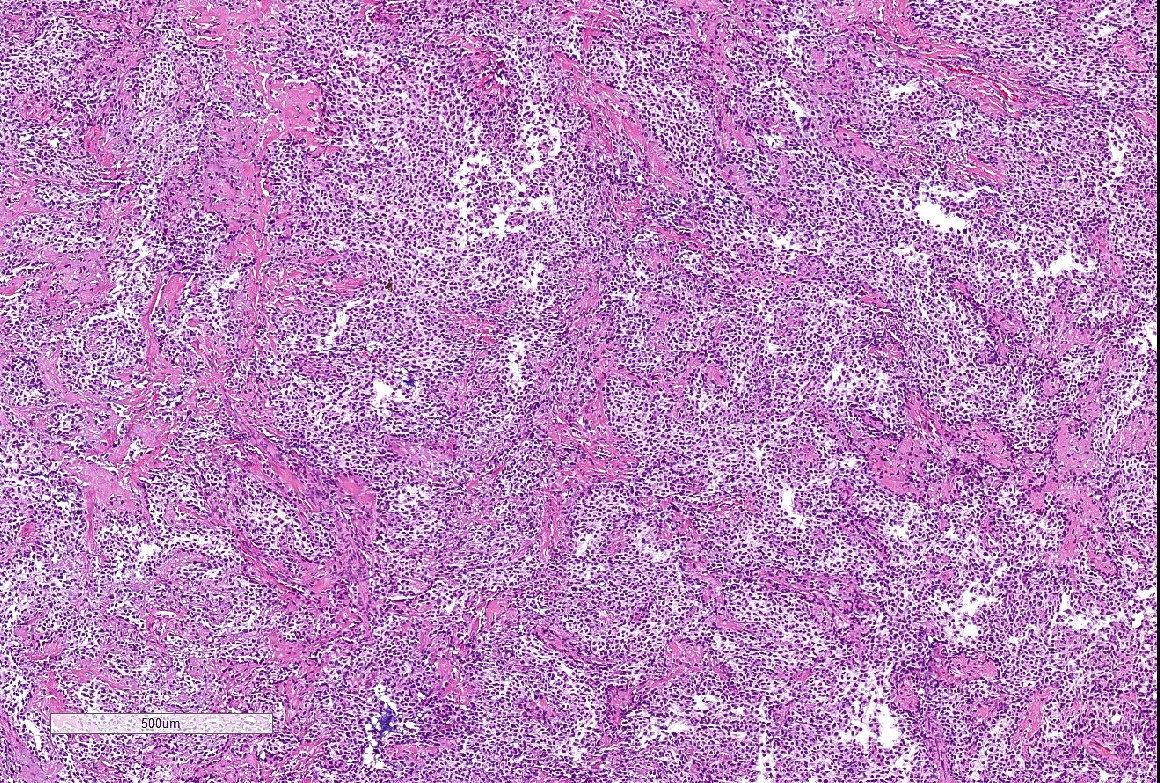

Microscopic (histologic) description

- Well demarcated tumor, often entrapped within skeletal muscle and frequently multilobulated (Am J Surg Pathol 2018;42:1297, Head Neck Pathol 2015;9:315)

- Stromal background may be hyalinized or demonstrate mucoid, myxoid or chondromyxoid areas

- Cords, strands or sheets of oval, round, fusiform or polygonal bland cells, sometimes arranged in a reticular / net-like or globoid pattern (Am J Surg Pathol 2018;42:1297)

- Myxoglobulosis-like changes have been noted (Virchows Arch 2003;442:302)

- May focally demonstrate fine calcifications, cellular atypia, necrosis, multinucleated giant cells (Am J Surg Pathol 2018;42:1297, Head Neck Pathol 2015;9:315, Oral Surg Oral Med Oral Pathol Oral Radiol Endod 1996;82:417)

- Cystic, slit-like spaces or hemorrhagic areas often noted (Head Neck Pathol 2014;8:329)

- Mitotic figures not seen (Head Neck Pathol 2015;9:315)

Microscopic (histologic) images